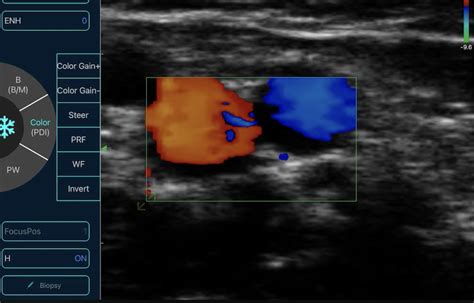

At its core, a home ultrasonography machine utilizes high-frequency sound beckon to create images of interior structures within the body. When the transducer (the handheld probe) is placed against the skin, it direct sound waves that jounce off organ, tissues, and fluids. The gimmick then beguile these echoes and converts them into clear image exhibit on a tablet, smartphone, or dedicated monitor.

• Assessing blood flow in trivial veins.